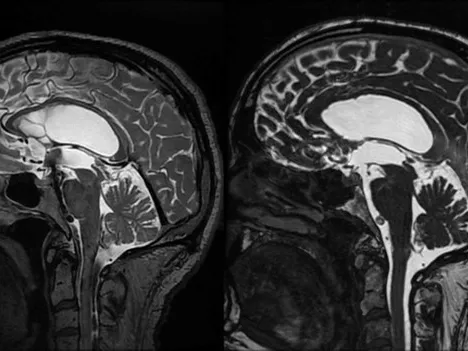

This fellowship will focus on a practical approach to applying knowledge of neuroanatomy in the radiological interpretation of normal anatomy as well as pathological conditions in the central nervous system.

The course will have three focus areas: anatomy of the brain and its connections, its vascular supply including collaterals and the CSF spaces, which become progressively important in diagnosis intracranial hypo- and hypertension.